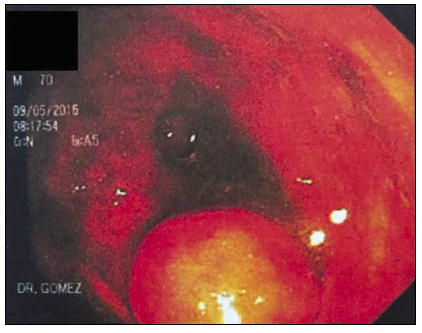

His physical examination was unremarkable. No abdominal tenderness, mass, or pain was found. During colonoscopy, an intraluminal round lesion, with a wide base located at the cecum in the appendix region, was found (Figure 1).

A tumor or polyp was suspected but, because of its size and the risk of leaving a posterior orifice that could complicate the patient`s prognosis, he was not colonoscopically intervened. Laboratory exams, including cell blood count and inflammatory markers where within normal parameters. The patient underwent a planned laparotomy via a McBurney incision. The findings revealed a nodular lesion of 1 to 1.5 cm implanted at the base of the appendix suggestive of an appendix tumor. The tumor and the appendix were removed through an appendectomy. Intra-operative cold biopsy was sent to the pathologist who reported an apparent mucinous cystoadenoma of the appendix. Abdominal cavity was closed and re-intervention was considered in case final histologic results changed. His postoperative course was uneventful. Histopathology reported a mucinous cystoadenoma macroscopically characterized by abundant mucinous material of white and transparent aspect with flattening of the mucosa and thinning of the walls (Figure 2).